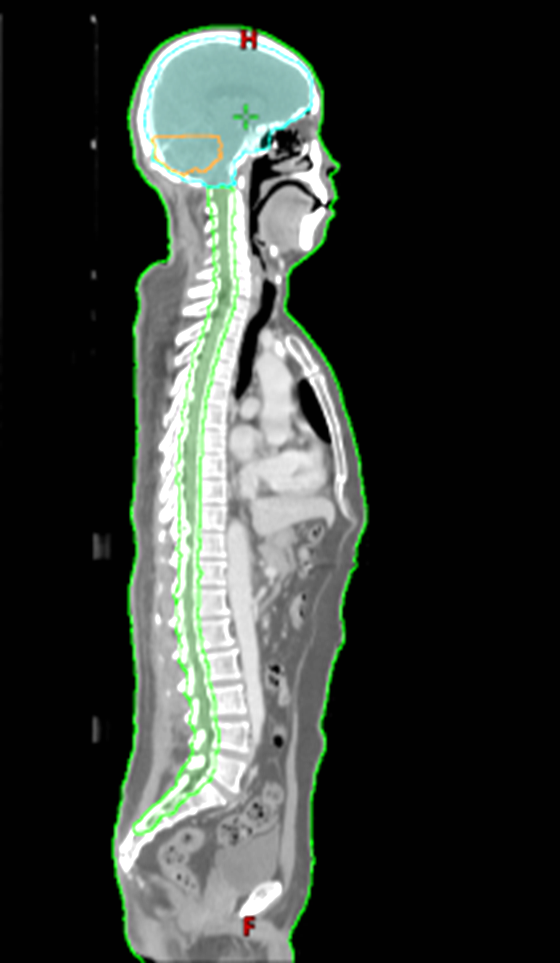

接诊后,肿瘤科钟美佐主任同秦勤主治医师联合神经外科、放射影像科、病理科根据病理诊断结果及患者实际情况反复讨论后决定实施全脑全脊髓放射治疗。考虑到照射范围长而复杂,肿瘤科放射治疗中心物理师医技团队使用一体板对患者进行全身固定,对全身采用多角度分段照射,在肿瘤接受足够照射的同时,保护脑干、晶体、视神经等重要正常器官。在治疗期间,医生、物理师、技术员会实时采集患者治疗时的体位影像,确保照射的安全准确。

全脑全脊髓照射区域长而广,在实施治疗时必须严格限制脑干、脊髓的照射剂量,避免相关后遗症的发生,保证患者的后期生活质量。肿瘤科放射治疗中心配备了瓦里安Trilogy直线加速器、Eclipse 13.6版本放疗计划设计系统和相关配套放疗定位装置,能对全身所有部位进行标准体位固定,精确计划设计和精准图像引导放射治疗。今后,肿瘤科还将继续加强同神经外科、病理科、放射影像科等相关临床科室交流协作,促进MDT多学科诊疗模式的快速发展,为患者制定全面化、专业化、规范化以及个体化的诊断治疗方案。